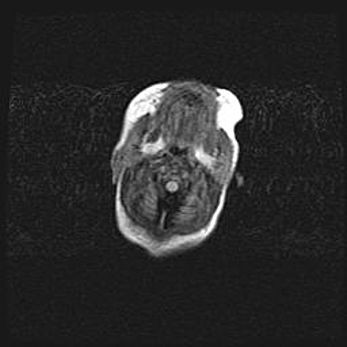

Аномалия Денди-Уокера. Признаки гипоплазии мозолистого тела.

Возраст: 5 месяцев 3 дня

Вес: 5550 г

Пол: мужской

Окружность головы: 39 см

Срок гестации: 40 недель

Аномалия Денди-Уокера – это порок развития головного мозга, для которого характерна триада симптомов: гипотрофия или аплазия червя мозжечка и/или полушарий мозжечка, расширение четвёртого желудочка с формированием ликворной кисты задней черепной ямки, гипертензионная гидроцефалия различной степени.

Гипоплазия мозолистого тела относится к дефектам внутриутробного этапа развития мозговой ткани, возникающим в процессе закладки структур головного мозга, что происходит на начальных этапах развития эмбриона.